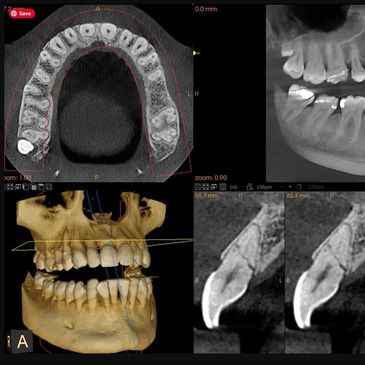

3D cone beam technology is an advanced imaging method that creates detailed three-dimensional images of your teeth and jaw. It captures high-quality images in a single scan, allowing us to see your teeth and jaw from different angles. This enhances diagnosis and treatment by providing clearer and more comprehensive views than traditional X-rays.